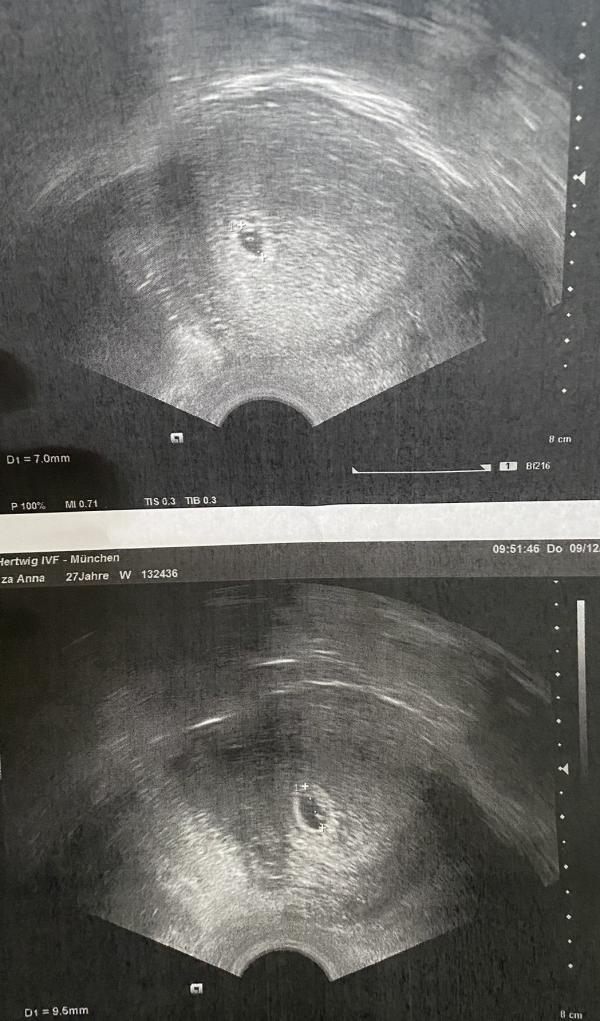

Я к вам опять с сюрпризом! Точнее сразу с двумя. Сегодня доктор на узи обнаружил два желточных мешочка. Что означает - двойня или близнецы. Конечно срок ещё очень маленький, неизвестно как будет дальше. У кого было так же, делитесь, что было потом? 😅❤️❤️❤️